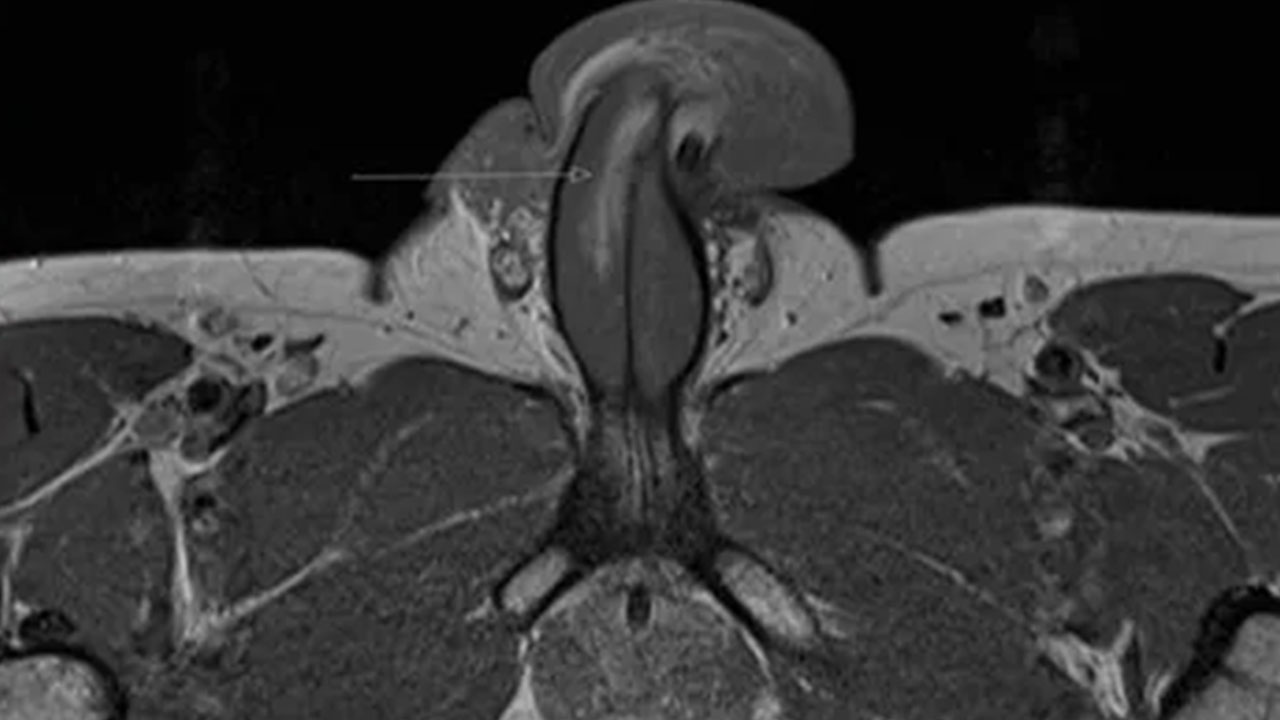

El caso fue extraño como para convencer a los médicos de que ordenaran una resonancia magnética, que generalmente no es necesaria en estos casos. Y cuando llegaron los resultados de la prueba, confirmaron que el pene del hombre tenía un desgarro vertical de tres centímetros de largo a lo largo del lado derecho, alrededor de la mitad del eje, en lugar de un desgarro transversal u horizontal. Por lo que saben, es la primera lesión de este tipo que se ha reportado. Desafortunadamente (o tal vez afortunadamente para los lectores), los médicos no tomaron ninguna foto de la lesión, debido a las restricciones relacionadas con la pandemia en la actualidad.

“En julio de 2020, una revisión de de PubMed confirmó que todos los casos documentados en el idioma inglés informan una fractura ‘transversal’ de la túnica albuginea”, escribieron los autores. “A su vez, presentamos el primer caso documentado de una fractura de pene vertical, confirmada en resonancia magnética, sostenida por un hombre de 40 años durante una relación sexual”.